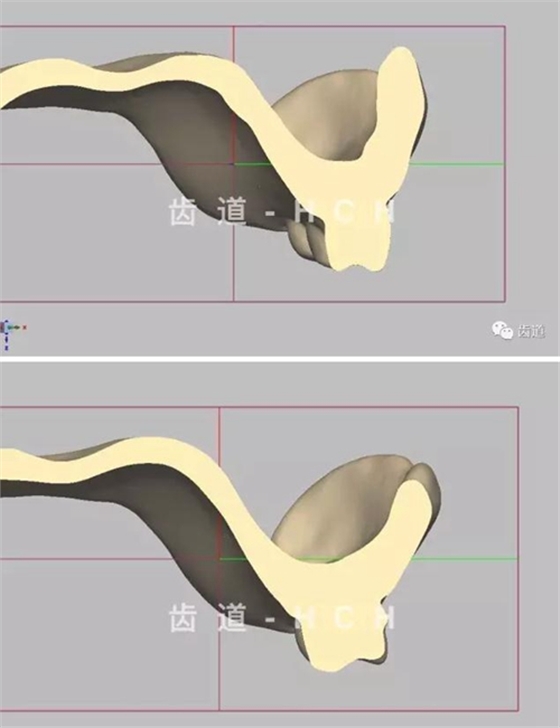

標(biāo)準(zhǔn)全口義齒模型截圖 科貿(mào)嘉友收錄